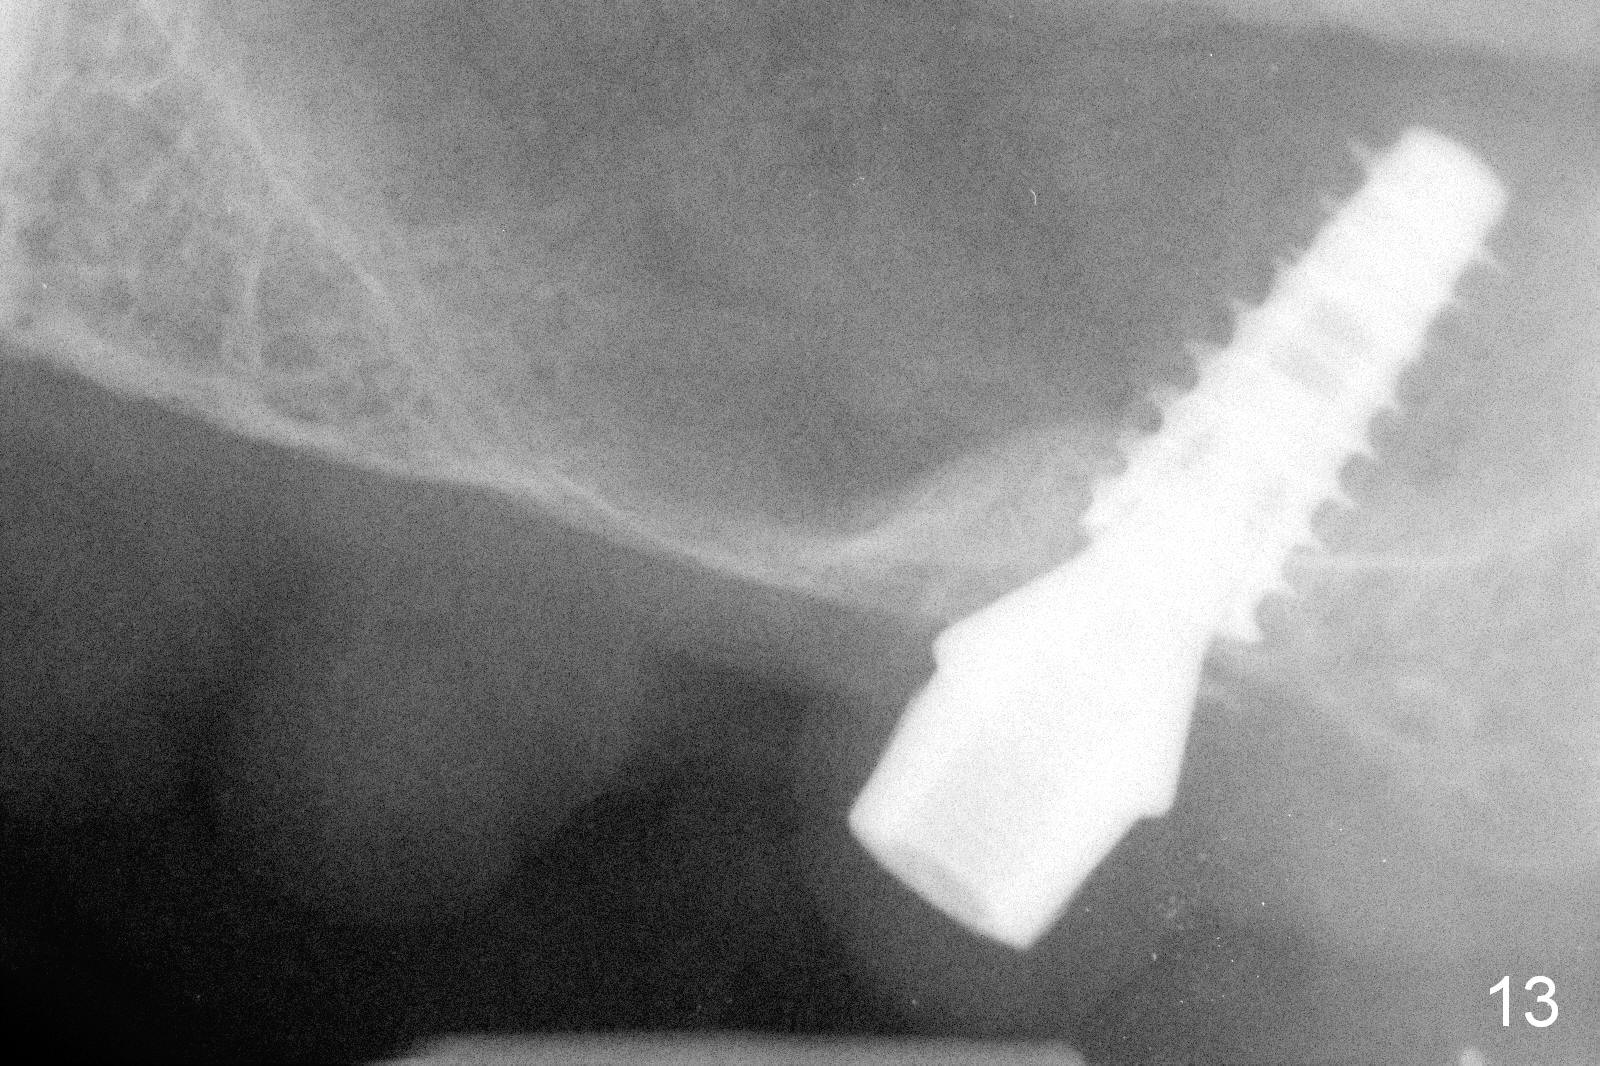

The bone density in the mesial socket appears to increase and becomes more homogenous 3 months postop (Fig.13).  Impression is taken for final restoration.